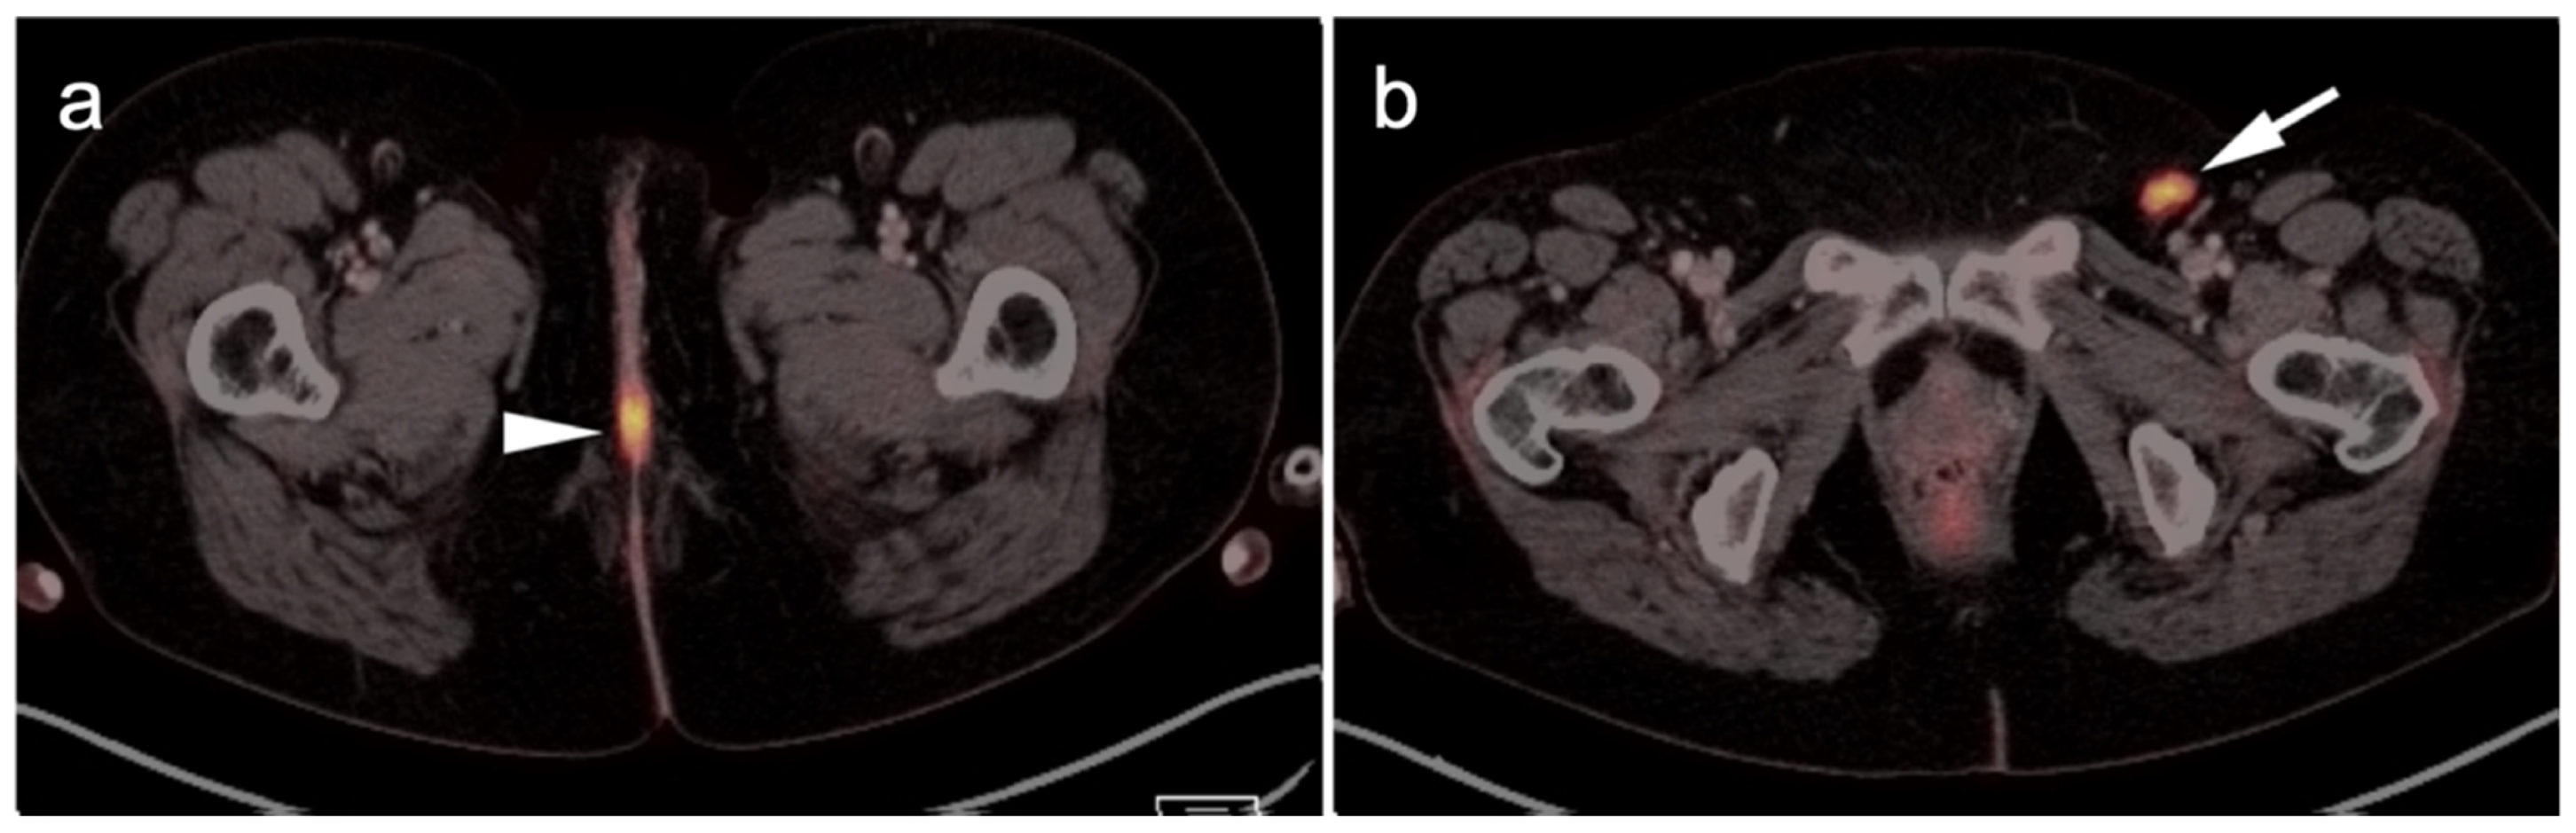

2.3.3. Mucosal Melanoma